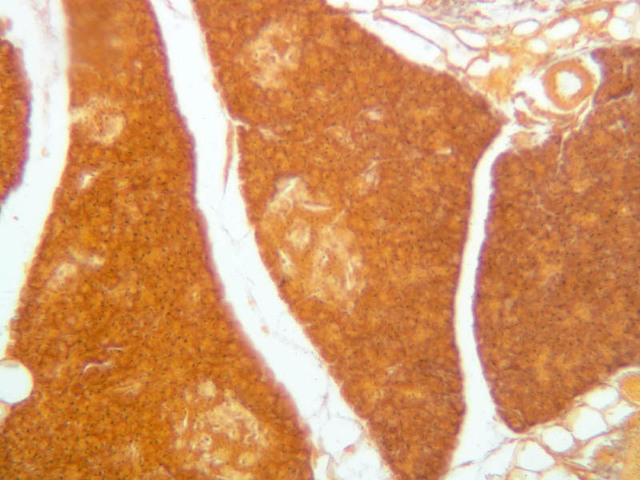

Study the distribution of glycogen in the sections of liver stained by the PAS method on slides B-31 ([2.5x-labeled, 10x, 20x, 40x] [2.5x, 10x, 20x, 40x-labeled]) and B-34 ([2.5x, 10x, 20x, 40x]. The tissue on slide B-34 was taken from an animal treated with glucagon. Had the specimens on slides B-31 and B-34 been prepared in a carefully controlled way, what difference would you expect to see in their glycogen deposits?